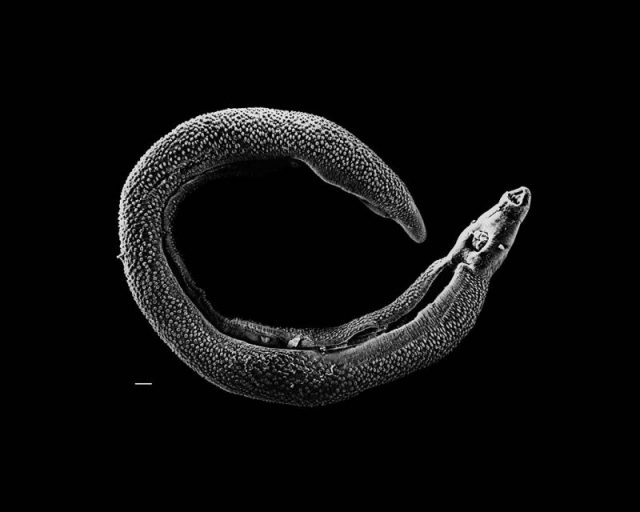

The infection comes from a type of microscopic trematode worm called Schistosoma, which has a complex life cycle. Just as the malaria parasite spends part of its life inside a mosquito, Schistosoma need a secondary host, in this case water snails, inside which their babies grow into teenagers. Now we get to the really gruesome part.

These teens burst out of the snail-host and swim around in fresh water lakes, rivers, ponds or streams, looking for a new home. A juicy human is exactly where they want to be; once they find one, they will burrow right through the person’s skin and into a blood vessel. But wait, it gets even more revolting. The next part can cause damage to various vital organs.

Once in the system, the Schistosoma migrate through their victim’s bloodstream to the liver, where they grow into adults and mate, before wiggling off to the intestines or bladder (depending on the species) to lay their eggs. The eggs leave the body by way of urine or feces, then hatch into larvae which start hunting for a water snail. And the terrible cycle begins again.

People prefer their parasites to be both out of sight and as far away as possible. The parasites (or “blood flukes” as they are charmingly referred to) have one side of that view covered. Now, thanks to the humble prawn, they may just be facing extinction.